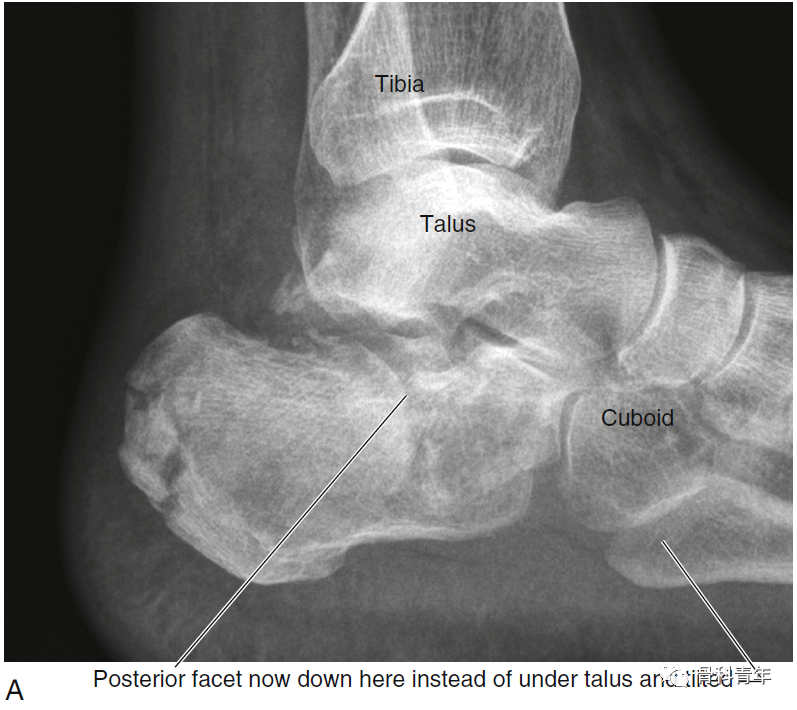

图:跟骨骨折,后关节面塌陷。

Gissane角:跟骨前后关节面之间的夹角,由跟骨外缘两条坚硬皮质骨柱的延长线构成,一条在后关节面的外缘,另一条位于前关节面的外侧,并向前延伸至跟骨前关节突的前部,正常范围在120-145°,该角度增大表明跟骨后关节面塌陷。

Böhler角:即跟骨结节关节面角。跟骨结节与跟骨后关节突连线,与跟骨前后关节突连线夹角,正常为35-45°。后关节面塌陷时该角减小。